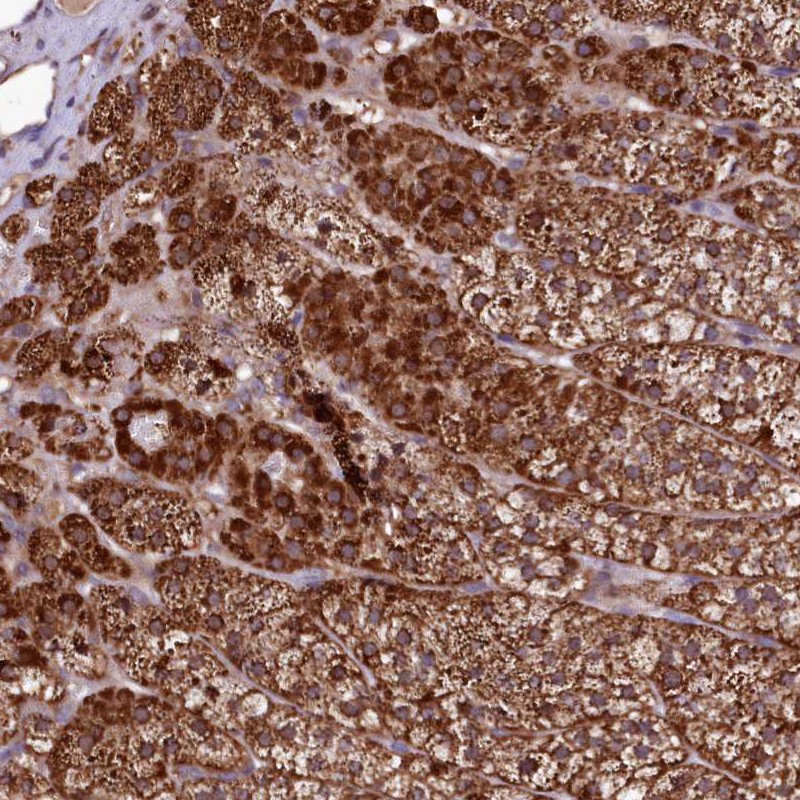

Immunohistochemical staining of human adrenal gland shows strong cytoplasmic positivity in cortical cells.